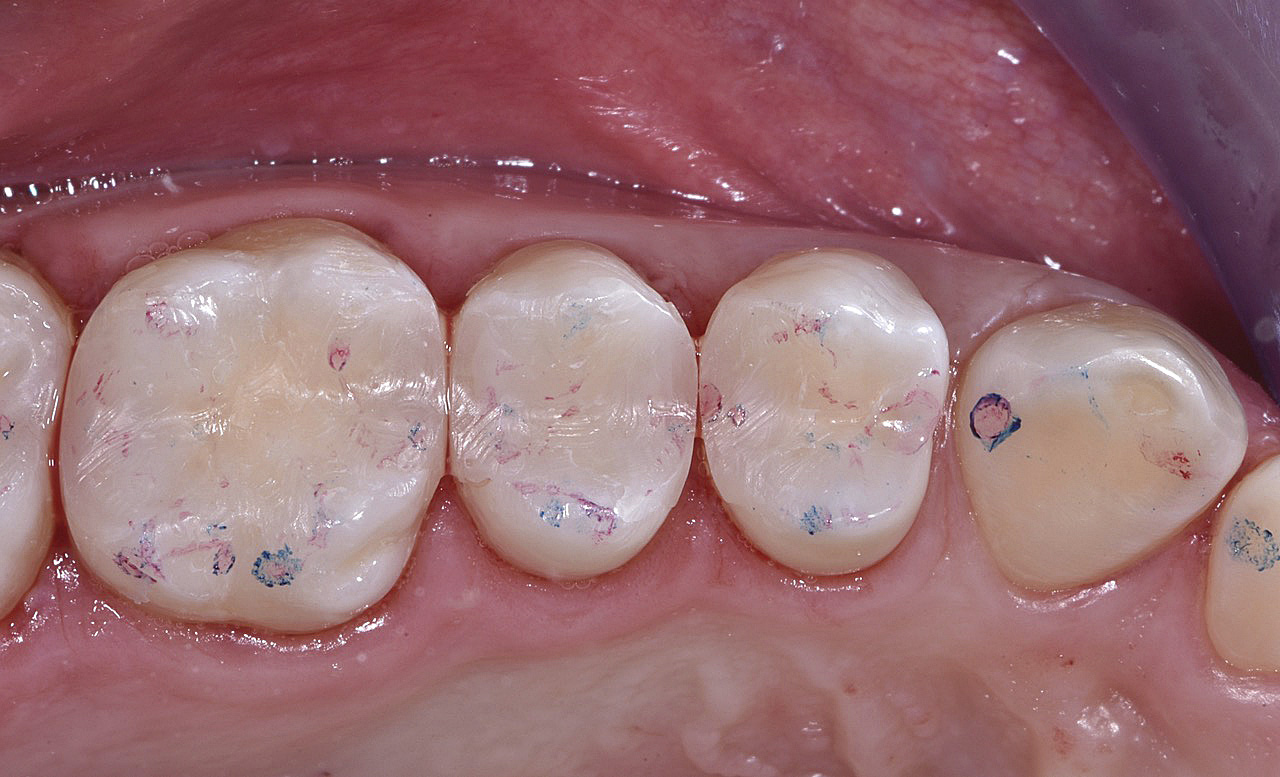

Vengono utilizzati 2 tipi di provvisori: il primo, cementato ai denti vicini, viene utilizzato dal momento dell’estrazione del dente fino ad impianto osteointegrato (circa 6 mesi); il secondo, avvitato direttamente all’impianto, ha una funzione di prova estetica ma soprattutto di guida per la maturazione dei tessuti gengivali peri-implantari portandoli verso la maturazione completa prima di posizionare la corona finale in disilicato di litio.